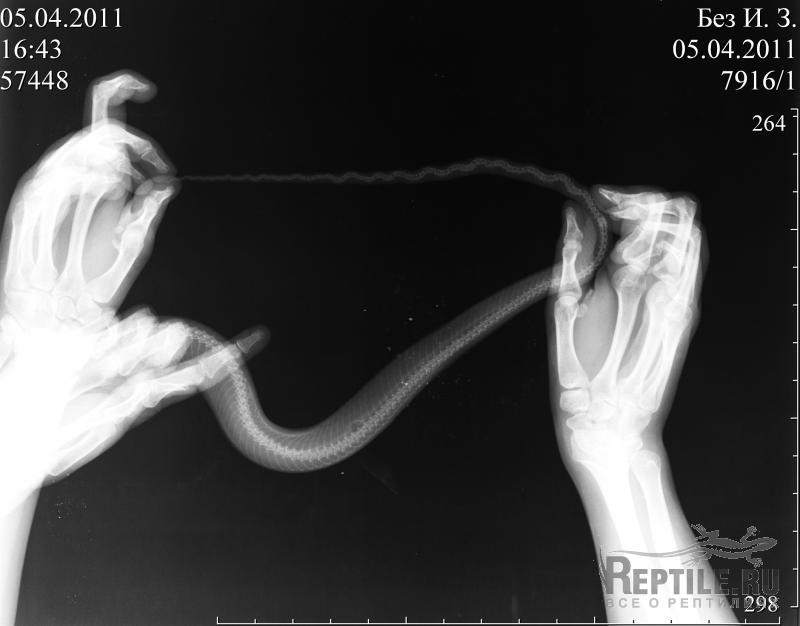

блин, шторы грязные. но в этой комнате кроме змеи никто не живёт.

прибавила в весе. ходили купаться в ванную, обезопасили от травматизма зубки змеи и своё лицо )